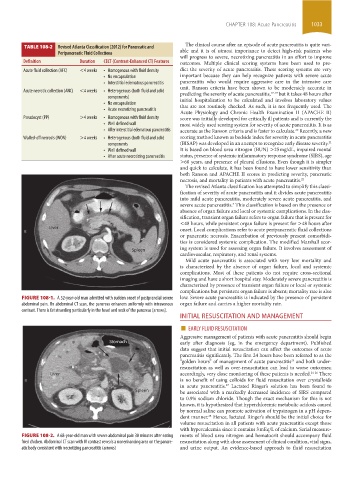

TABLE 108-2 Revised Atlanta Classification (2012) for Pancreatic and

Peripancreatic Fluid Collections able and it is of utmost importance to detect high-risk patients who

Definition Duration CECT (Contrast-Enhanced CT) Features outcomes. Multiple clinical scoring systems have been used to pre-

Acute fluid collection (AFC) <4 weeks • Homogenous with fluid density dict the severity of acute pancreatitis. These scoring systems are very

• No encapsulation important because they can help recognize patients with severe acute

• Interstitial edematous pancreatitis pancreatitis who would require aggressive care in the intensive care

Acute necrotic collection (ANC) <4 weeks • Heterogenous (both fluid and solid predicting the severity of acute pancreatitis, 17-19 but it takes 48 hours after

components) initial hospitalization to be calculated and involves laboratory values

• No encapsulation that are not routinely checked. As such, it is not frequently used. The

• Acute necrotizing pancreatitis

Pseudocyst (PP) >4 weeks • Homogenous with fluid density score was initially developed for critically ill patients and is currently the

• Well defined wall most widely used scoring system for severity of acute pancreatitis. It is as

• After interstitial edematous pancreatitis accurate as the Ranson criteria and is faster to calculate. Recently, a new

Walled-off necrosis (WON) >4 weeks • Heterogenous (both fluid and solid scoring method known as bedside index for severity in acute pancreatitis

components (BISAP) was developed in an attempt to recognize early disease severity.

• Well defined wall It is based on blood urea nitrogen (BUN) >25 mg/dL, impaired mental

• After acute necrotizing pancreatitis status, presence of systemic inflammatory response syndrome (SIRS), age